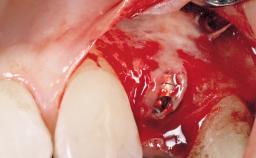

Late Flapless Placement of an Implant in a Maxillary Left Central Incisor Site

Bone Augmentation Horizontal|Staged

Augmentation Materials Xenogenous|Membrane

Soft Tissue Grafting Simultaneous